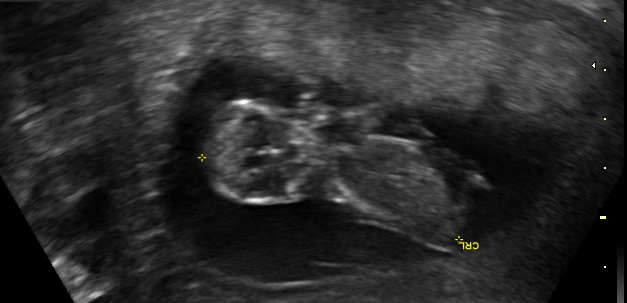

I was 11w5d when I had the scan, although I was measuring 12w1d. I know it's still pretty early, but am wondering if you see anything on these (terrible quality) scan pics! Attachment 23572Attachment 23571Attachment 23573Attachment 23574Attachment 23575